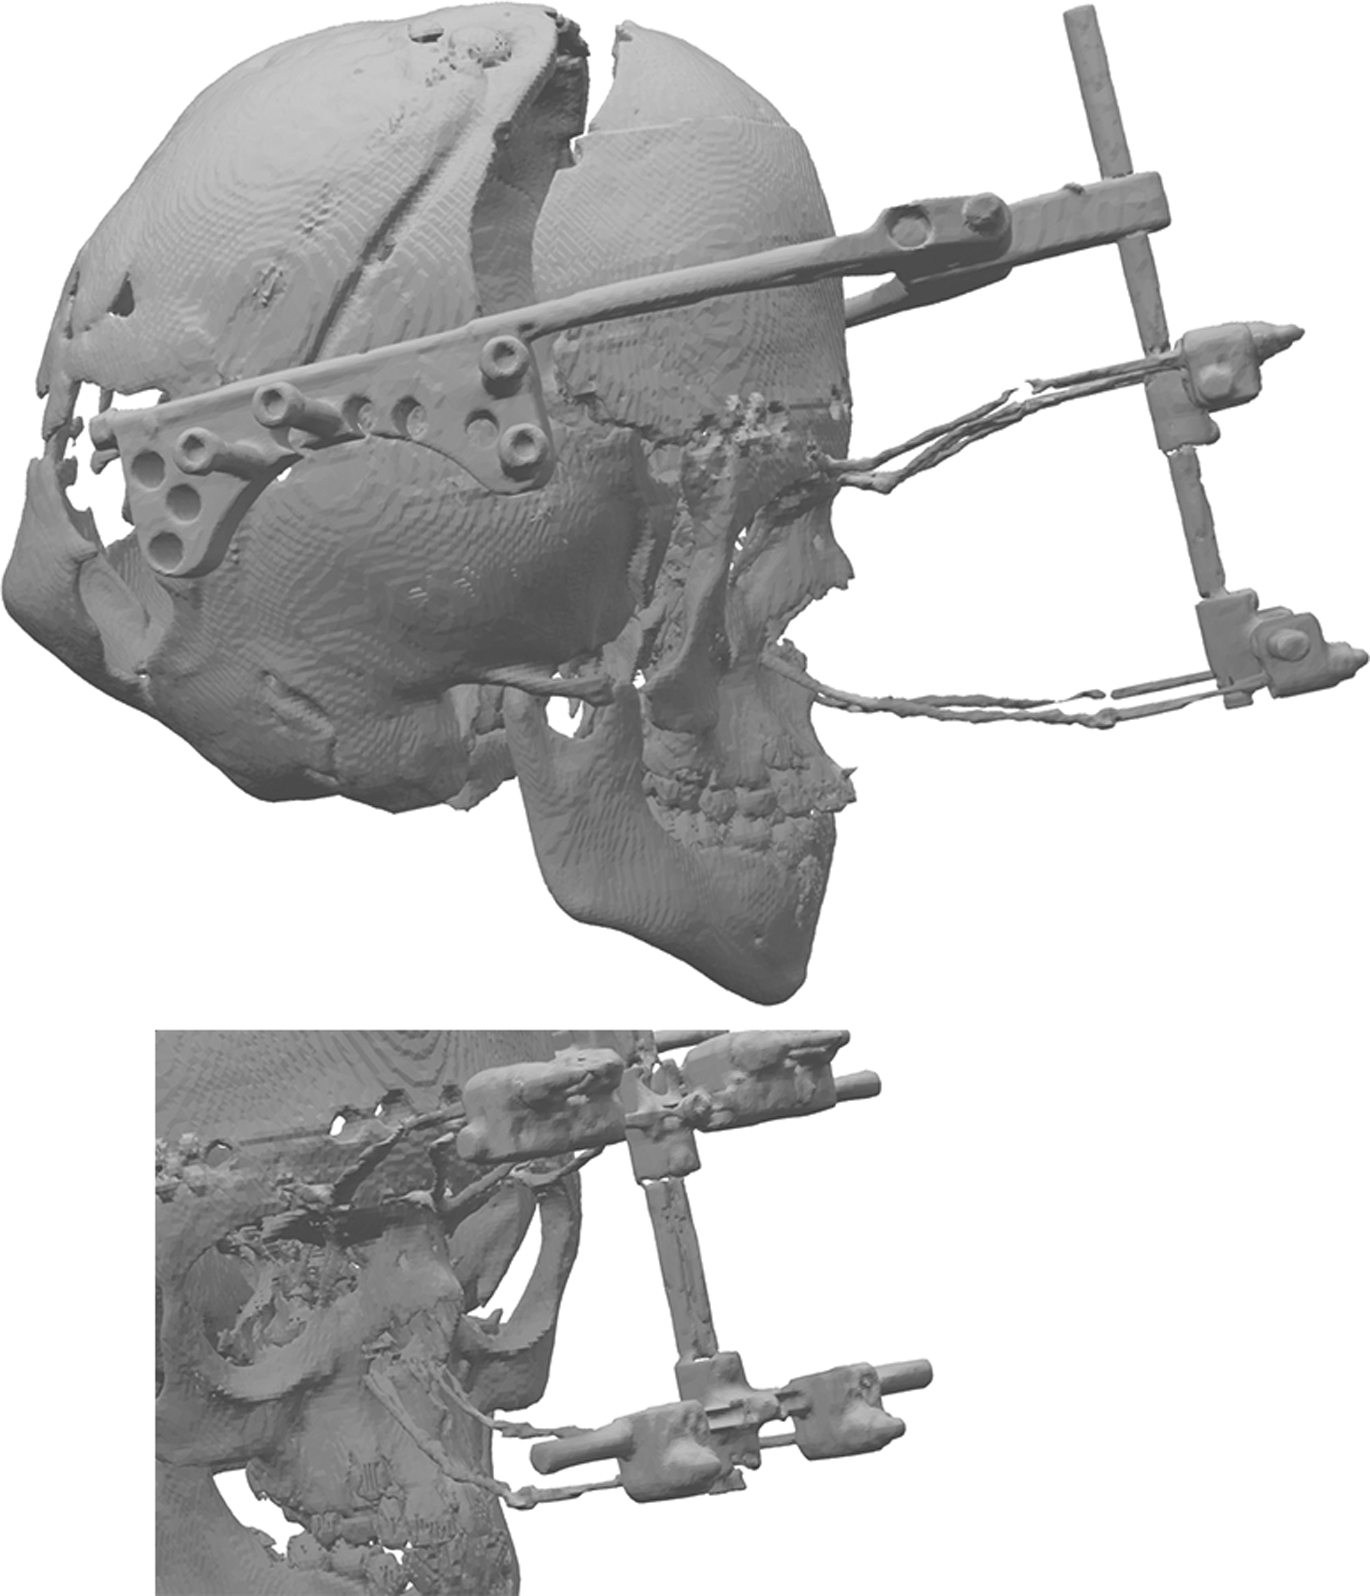

Attachments for the distractor wire are now placed using a combination of drill holes and titanium plates. Our preference is generally to place 3 fixation points above the orbit positioned in the midline and just lateral to the supraorbital notch. Fixation at the lower maxillary level is through drill holes in the inferior lateral part of the piriform aperture ( Fig. 2 ). Many clinicians prefer the use of a fixation to the upper dental arch using a splint, which is an effective method, but, in our experience, the pyriform aperture wires are more comfortable for the patient.